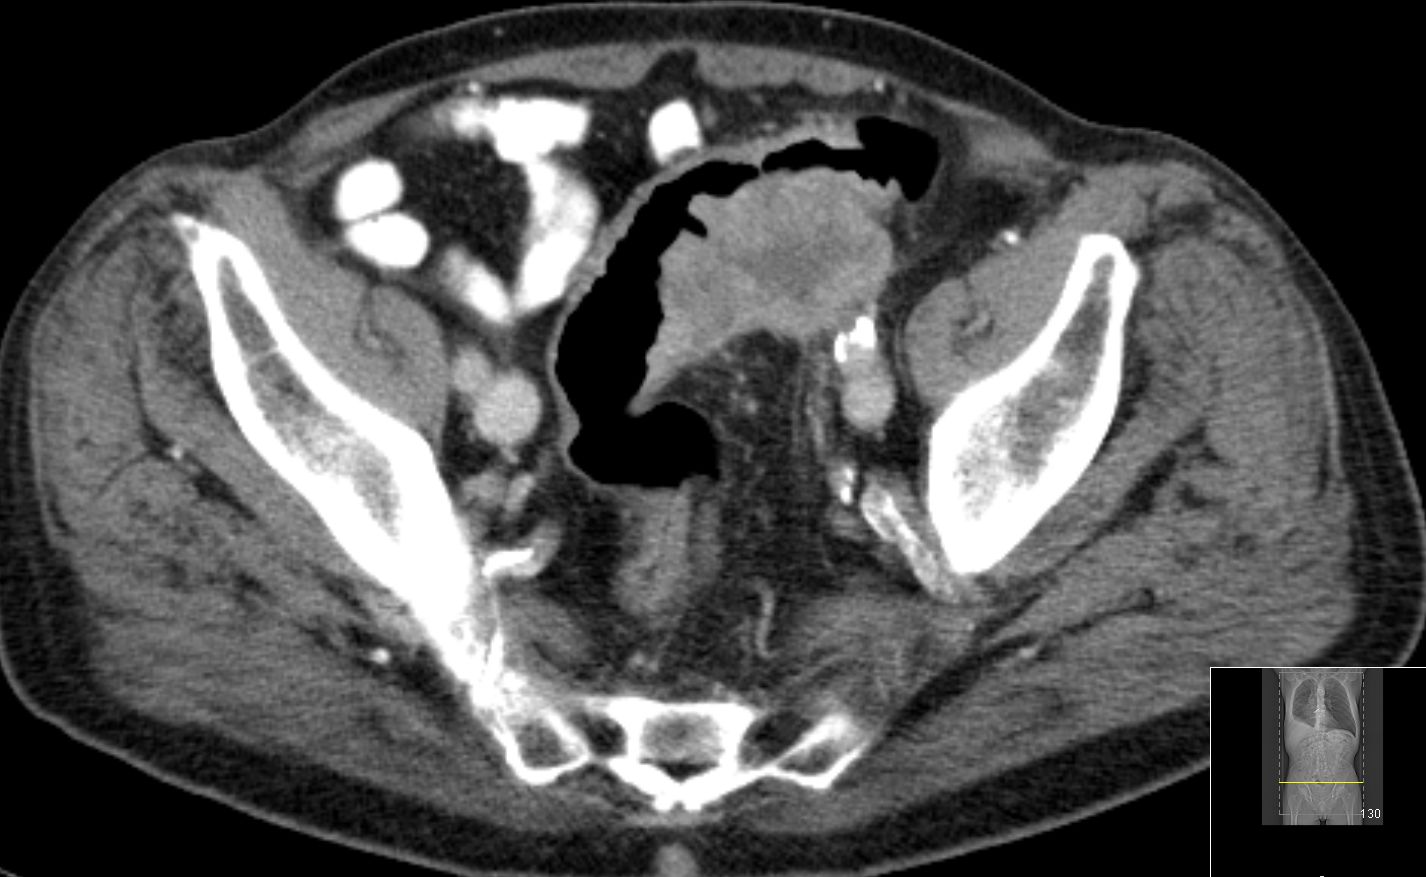

| Knochenmetastasen | Die dorsalen Hüftpfannenteile links und Teile des Sitzbeins sind völlig zerstört.![]() |